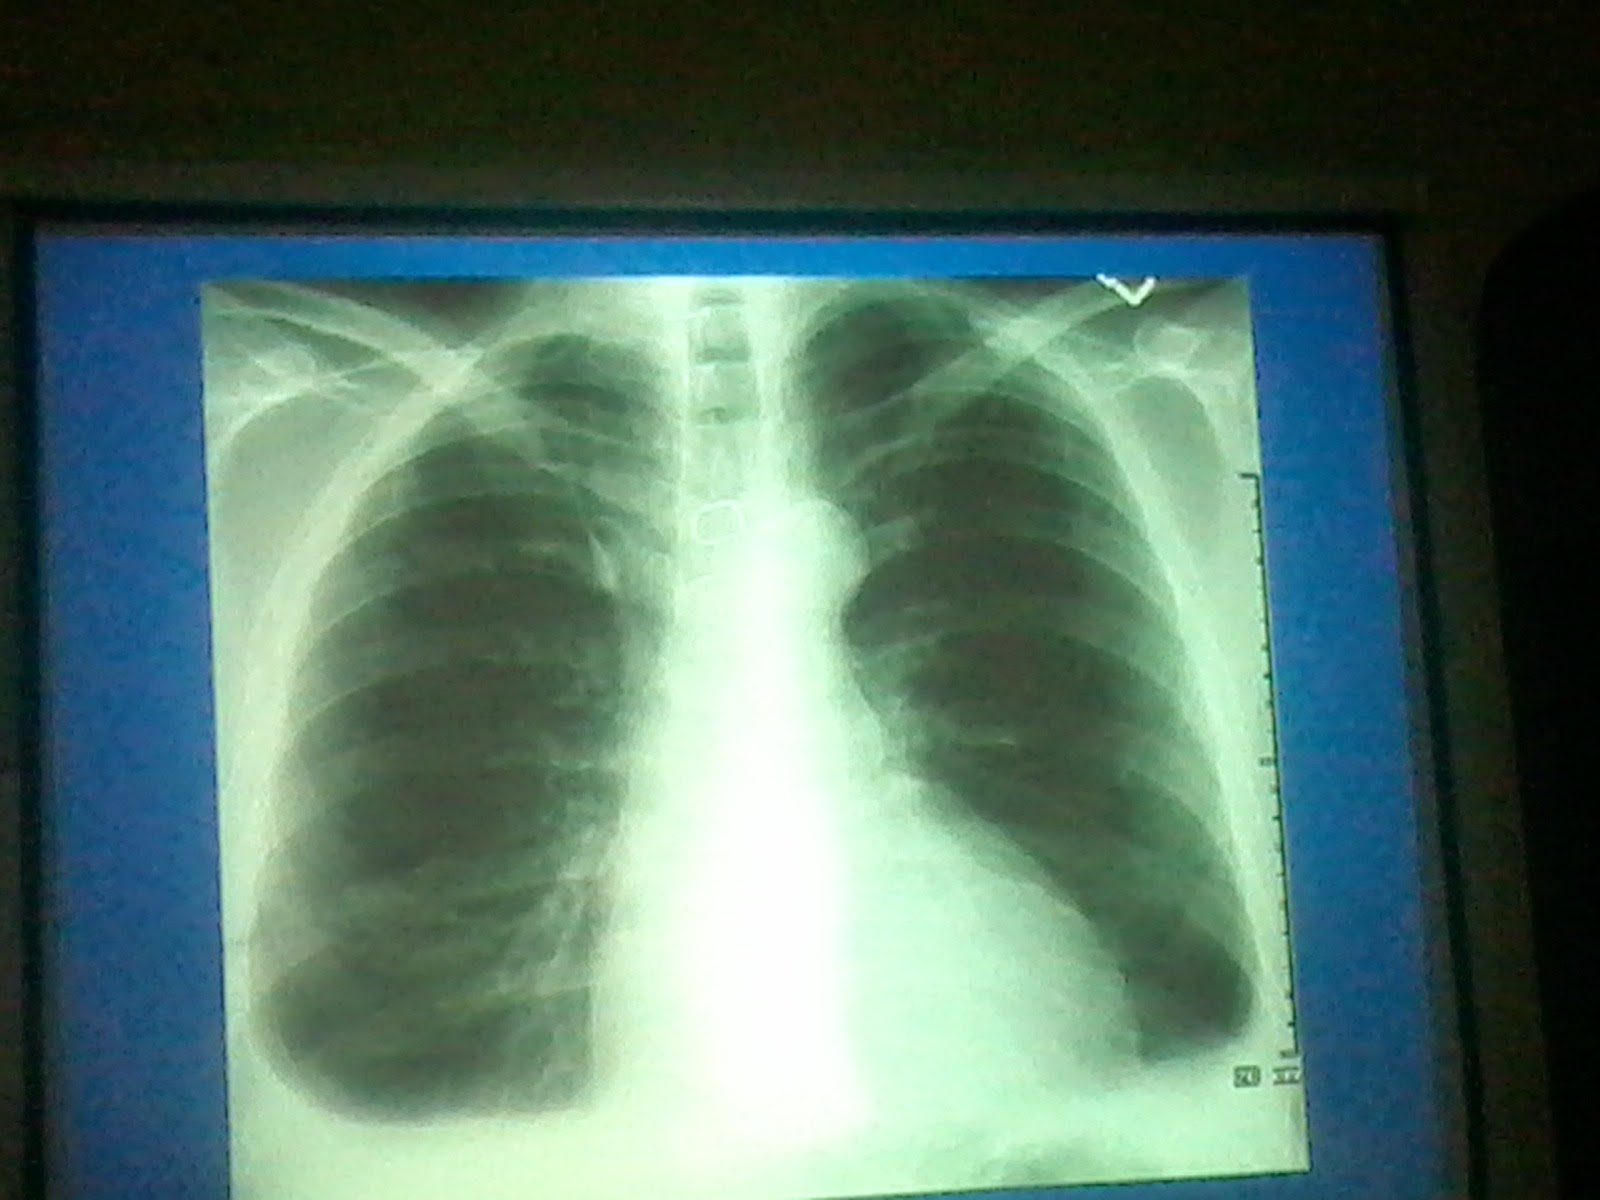

From www.kemunited.com

Lecture slides Radiology Chest X ray Chest X Ray Lecture In fact every radiologst should be an. — a description of a systematic method for examining a chest x. Understand the key concepts of reading a chest radiograph with this. a free medical lecture on chest x ray (cxr) interpretation. Chest X Ray Lecture.